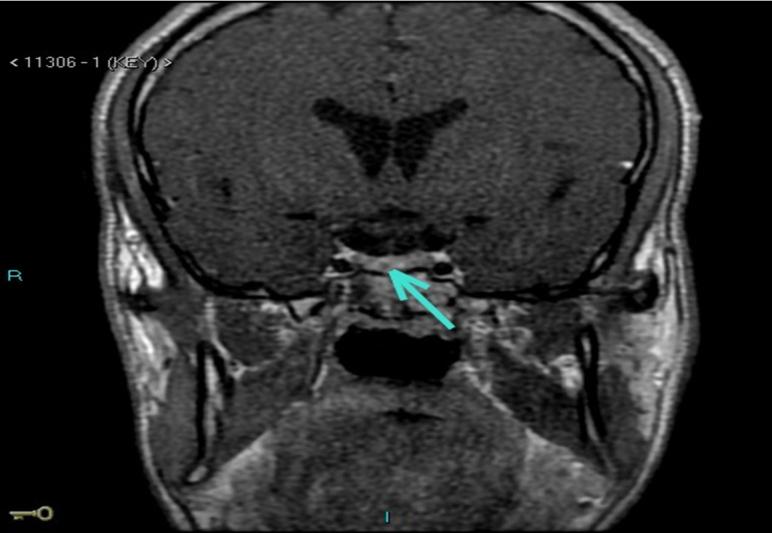

Acromegaly is characterized by excess skin and soft tissue growth due to increased growth hormone (GH) levels. Patients with similar physical findings but without somatotroph axis abnormalities are considered to have pseudoacromegaly. The list of pseudoacromegaly differential diagnoses is long. It may be caused by several congenital and acquired conditions and diagnosis can be challenging due to its rarity and occasional overlapping of some of these conditions. The presence of a pituitary tumour in such cases may lead to a misdiagnosis of acromegaly, and thus, biochemical evaluation is key. Here, we present a case of pseudoacromegaly with an acromegaloid phenotype, normal IGF levels, a supressed GH response to an oral glucose tolerance test, moderate insulin resistance and non-functioning pituitary microadenoma.

肢端肥大症的特征是由于生长激素(GH)水平升高导致皮肤和软组织过度生长。具有相似体格检查结果但无生长激素轴异常的患者被认为患有假性肢端肥大症。假性肢端肥大症的鉴别诊断清单很长。它可能由多种先天性和后天性疾病引起,由于其罕见性以及其中一些疾病偶尔会重叠,诊断可能具有挑战性。在这种情况下存在垂体肿瘤可能导致肢端肥大症的误诊,因此,生化评估是关键。在此,我们报告一例具有肢端肥大样表型、正常胰岛素样生长因子(IGF)水平、口服葡萄糖耐量试验时生长激素反应受抑制、中度胰岛素抵抗和无功能垂体微腺瘤的假性肢端肥大症病例。